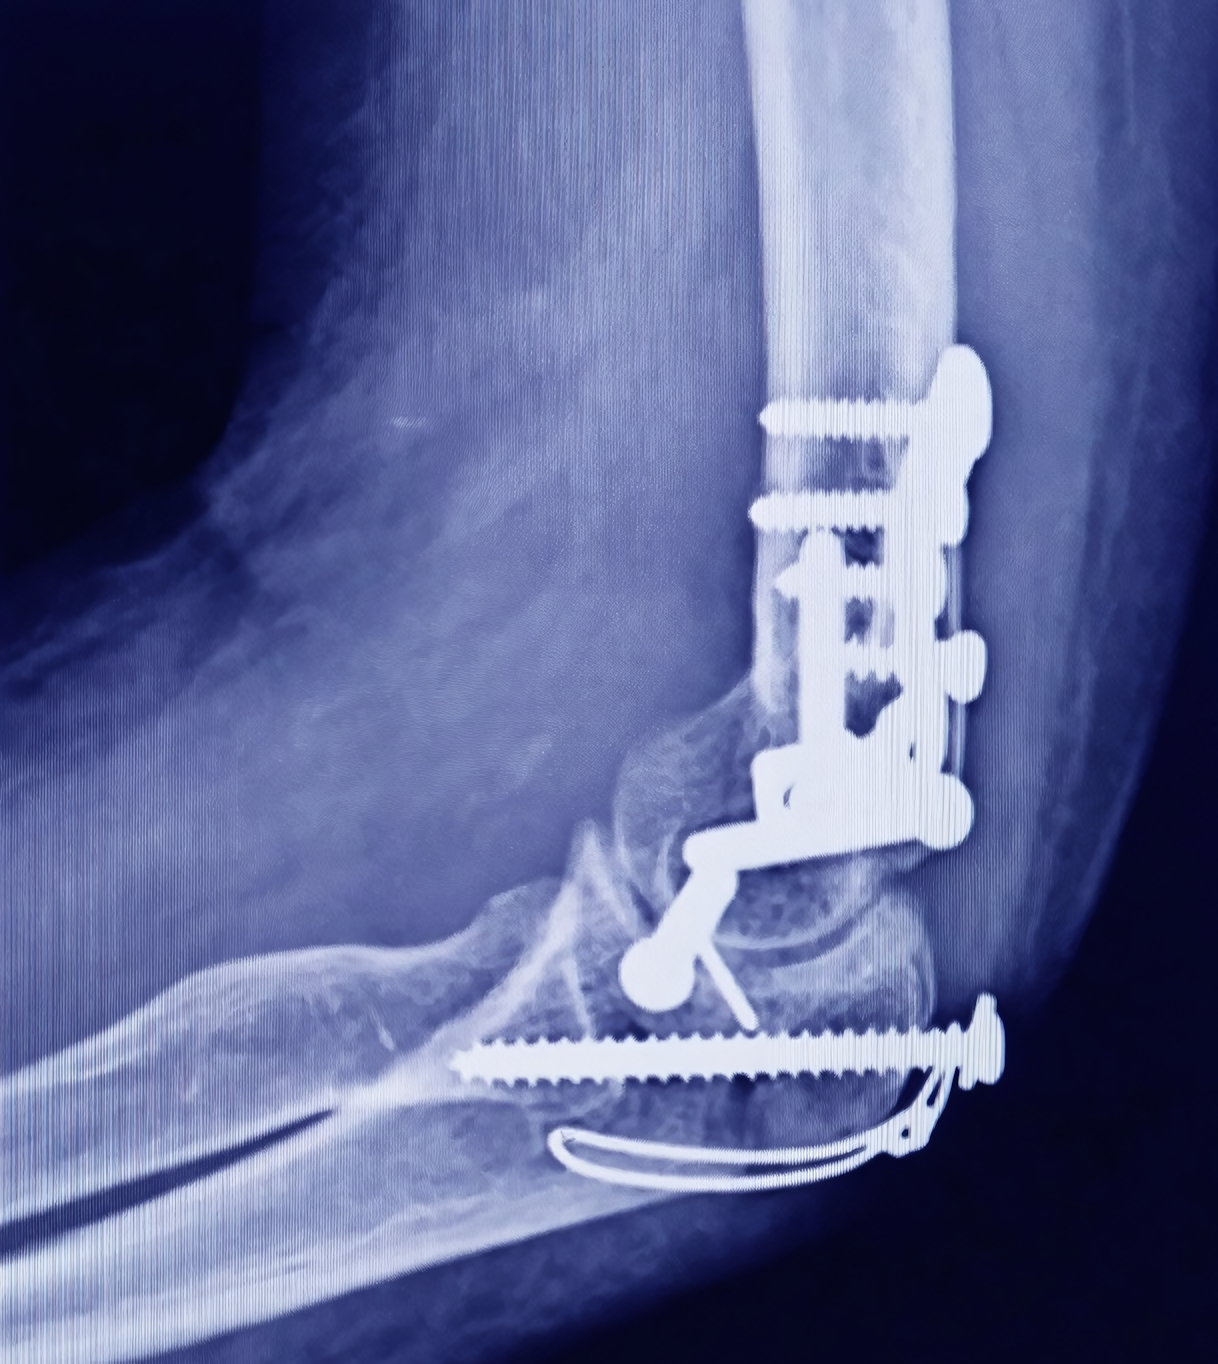

El área de trauma ortopédico se especializa en la atención de pacientes que han sufrido fracturas, luxaciones o lesiones complejas derivadas de caídas, accidentes laborales, deportivos o de tránsito. Nuestro equipo interdisciplinario aplica protocolos de atención inmediata para reducir riesgos y complicaciones, ofreciendo desde tratamientos conservadores hasta procedimientos quirúrgicos avanzados. Además, acompañamos el proceso de recuperación con terapias orientadas a recuperar la movilidad y prevenir secuelas.

¿Todas las fracturas requieren cirugía?

No. Muchas fracturas pueden tratarse de manera conservadora mediante inmovilización y control médico. La cirugía se recomienda cuando los huesos están desplazados, hay compromiso articular, lesiones múltiples o riesgo de mala consolidación. El médico evaluará el tratamiento más seguro y funcional según cada caso.